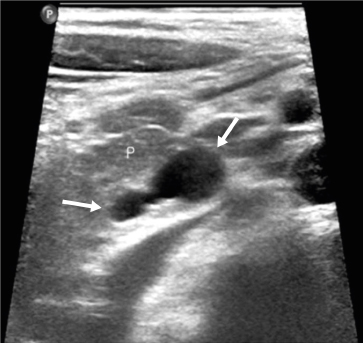

The initial preoperative laboratory data revealed an elevated amylase of 153 U/L and a lipase level of 71 U/L. The liver function tests were otherwise normal except for an elevated alkaline phosphatase of 429 IU/L. Abdominal ultrasonography was performed, which showed a lobulated cystic mass in the pancreas (Fig. 1), and subsequent computerized tomography (CT) showed a mildly inflamed pancreas with a 1.2×0.9×1.3 cm-sized low-attenuating cystic lesion with a pleomorphic appearance at the pancreatic uncinate process (Fig. 2). A magnetic resonance imaging (MRI) scan performed later for cystic evaluation showed pancreatic ductal communication with the cystic lesion along with downstream ductal dilatation. Furthermore, mild dilatation of the main pancreatic duct was observed (Fig. 3). The cystic lesion revealed communication with the dorsal duct and congenital anomaly of the pancreatic duct, and pancreas divisum was suspected due to a lack of fusion of the ventral and dorsal ducts and the common bile duct, which joins with the dorsal duct. Therefore, given the suspicion of IPMN and symptoms of pancreatitis, the patient underwent a pylorus-preserving pancreaticoduodenectomy. The histopathology report revealed BD-IPMN with intermediate-grade dysplasia. The depth was limited to the pancreas without invasion of the surrounding adjacent organs. Pancreatic intraepithelial neoplasia was not applicable, and the mucinous glands were of the intestinal type (Fig. 4).

Fig. 1

Abdominal ultrasonography reveals a lobulated cystic mass (arrows) without discernable solid components.